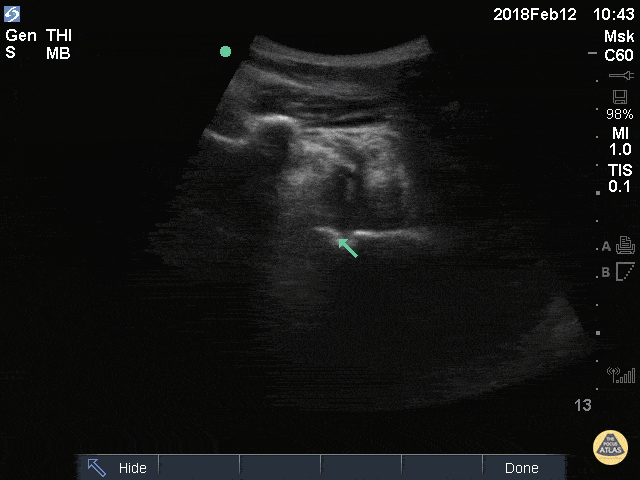

50M w/ R shoulder dislocation (arrow over humeral head), also likely has blood and possible air in joint space from injection of anesthetic. Greg Powell, MD